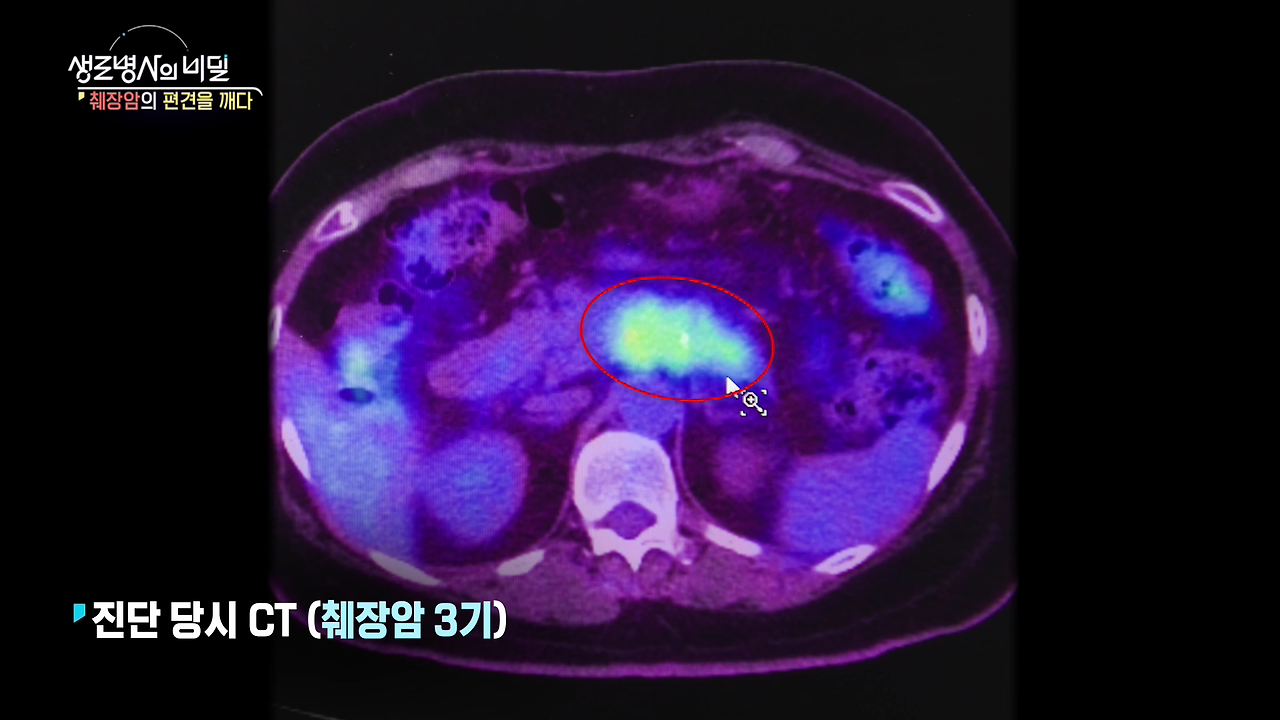

3기 췌장암 진단을 받은 **김정숙 씨(60)**는 고통스러운 항암 치료 대신

빛의 속도로 암세포를 정밀 타격하는 중입자 치료를 선택했습니다.

정확도와 효과 면에서 기존 방사선 치료보다 뛰어난 이 치료법,

과연 누구에게 적합한 방법일까요?